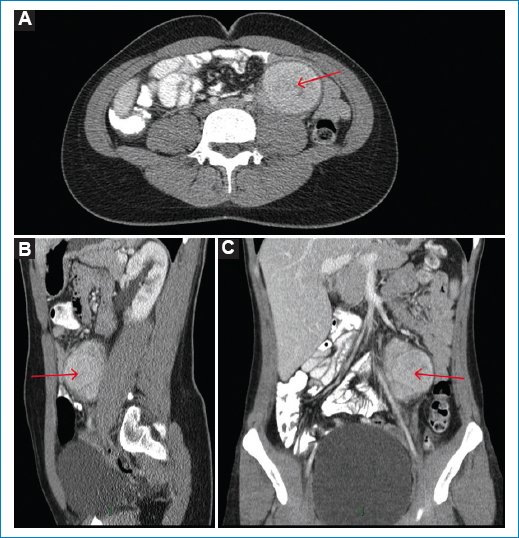

Se trata de una mujer de 25 años con antecedente de hipotiroidismo que consultó por una masa palpable en el mesogastrio, sin dolor ni otros síntomas gastrointestinales. Se realizó ecografía de abdomen que mostró una masa sólida, retroperitoneal, paraaórtica izquierda, adyacente al músculo psoas. Se complementó entonces con tomografía computada (TC) de abdomen contrastada, encontrando una masa de 8 × 5,6 cm, con realce homogéneo con el medio de contraste, sin zonas de necrosis ni calcificaciones, sin invadir las estructuras adyacentes y en estrecha relación con el músculo psoas (Fig. 1). Se solicitó una resonancia magnética (RM) contrastada para mejor caracterización. Dicha masa presentaba intensidad de señal homogénea, isointensa en T2, hipointensa en T1, con restricción a la difusión (alta señal en el DWI y baja señal en el ADC), y realce temprano homogéneo e intenso con el medio de contraste (Fig. 2), asociado a varios ganglios retroperitoneales. Se sugirió como primera posibilidad linfoma retroperitoneal. Se realizó biopsia y resección de ganglio retroperitoneal, con reporte de patología de enfermedad de Castleman hialinovascular.

Figura 1. TC de abdomen con contraste en fase venosa en plano axial (A), sagital (B) y coronal (C). Se observa una masa redonda, retroperitoneal, paraaórtica izquierda (flechas rojas), que mide 8 × 5.6 × 4.6 cm, adyacente al músculo psoas, con realce homogéneo con el medio de contraste, sin calcificaciones ni zonas de necrosis. No hay invasión de las estructuras adyacentes.